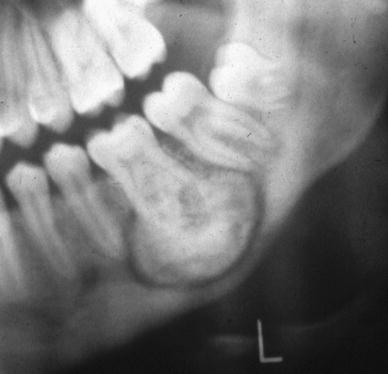

Fig. 3

Cementum with basophilic reversal lines and intervening loose fibrovascular connective tissue stroma

Fig. 4

Cementum with prominent cementoblastic rimming

I would like to give credit to Dr. Dave Wells, D.D.S., M.S. for providing the images of figure 3 and 4.